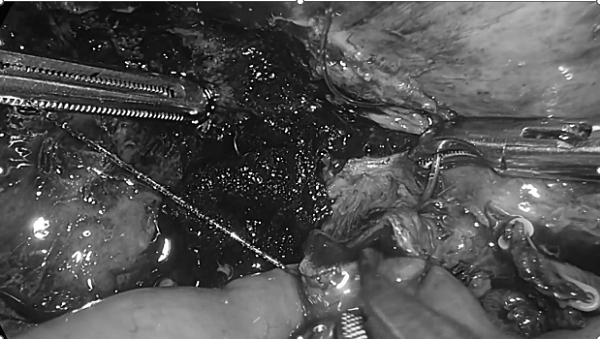

术前,陈艳军主任医师团队再次进行周密讨论,聆听患者及家属意愿,考虑患者对生活质量的强烈要求,结合腹腔镜手术具有创伤小、解剖精准、术后恢复快的优势,在得到患者家属充分信任及认同后,决定行腹腔镜下肝门部胆管癌根治术。在麻醉科胡强夫主任麻醉团队及手术室刘丹丹护士长护理团队的配合下,陈艳军主任医师团队按照肝门部胆管癌根治术标准,耐心细致地实施肝门部组织的解剖,游离腹腔粘连组织,清扫相关淋巴结,切除胆囊,切除胆管、保证上下切缘阴性,将肝门部左右肝管成形,最后使用切割闭合器离断空肠,远端空肠与肝管行胆肠吻合术、距胆肠吻合口50cm处与空肠近端行侧侧吻合术,每个步骤都是严峻的挑战,术中密布“雷区”,经过五个小时的努力,顺利完成全腹腔镜下肝门部胆管癌根治术,出血量不足50ml,手术进展十分顺利。术后经过精心护理,患者未出现严重并发症,黄疸情况迅速改善,于术后第9天顺利出院。

3.胆肠吻合